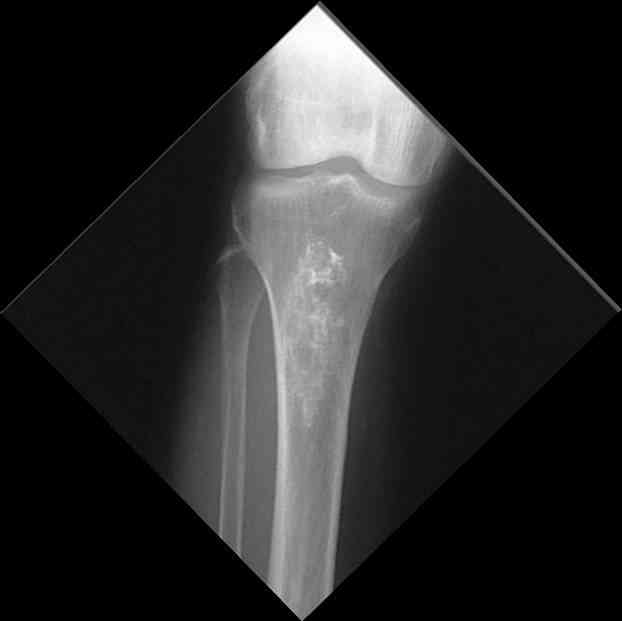

Изменения структуры костей у Вашего пациента больше похожи на

полиоссальную форму фиброзной дисплазии или болезнь Педжета, возможены

также инфаркты костного мозга б.берцовых костей. К сожалению, качество

снимка не очень хорошее, не понятно, сохранен ли кортикальный слой

б.берцовых костей по передней поверхности.

Для примера привожу случай из архива американской ассоциации

рентгенологов (ACR) - развитие злокачественной фиброзной гистиоцитомы

на левой б.берцовой кости у пациента с множественными инфарктами

костного мозга (рис 4,5 - левая, рис 6 - правая)